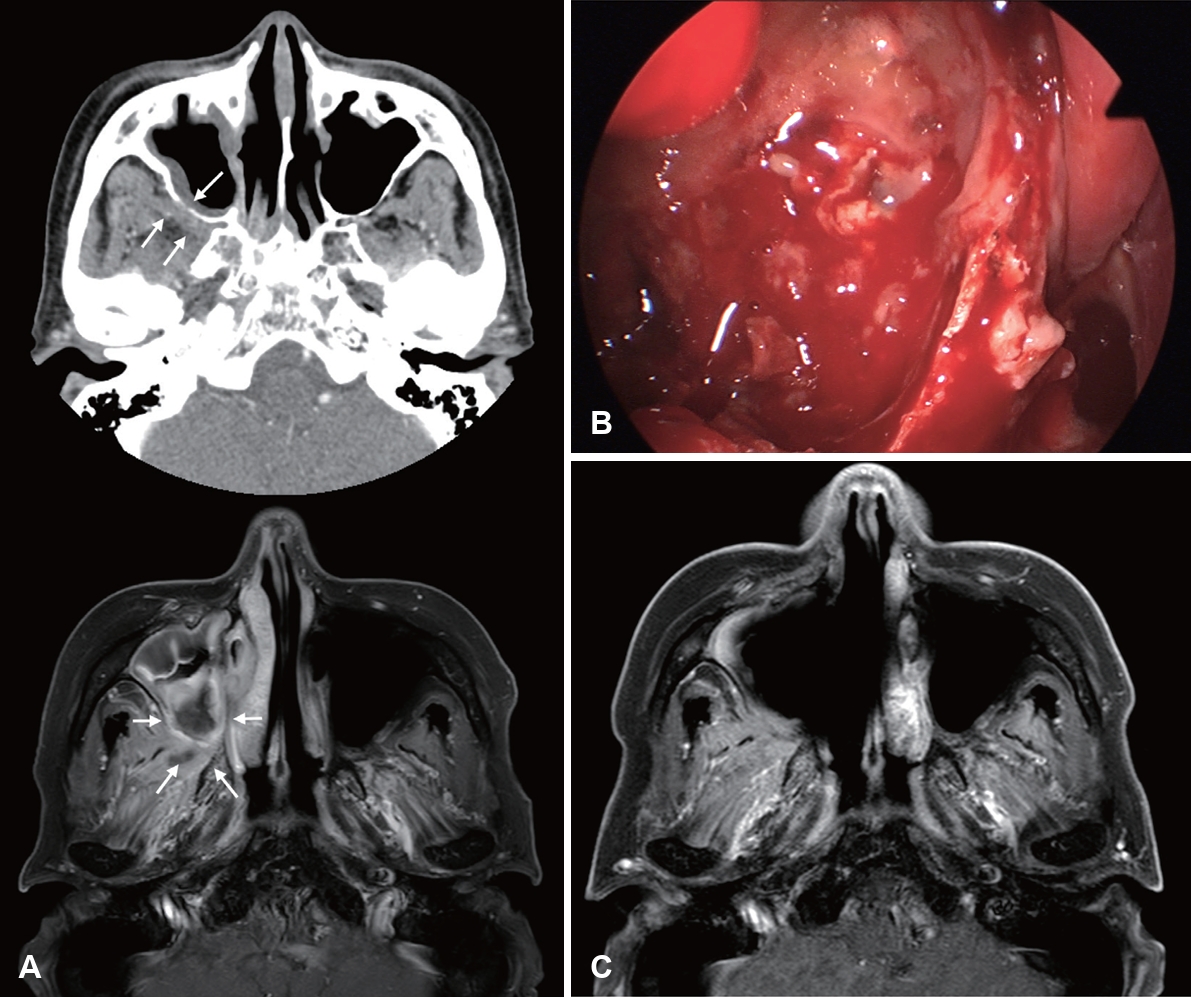

Image findings of CIFRS and CGIFRS are distinguished from those of AIFRS. CIFRS showed diffuse infiltrative patterns, whereas CGIFRS showed mass-forming patterns. The infiltrative pattern of CIFRS is characterized by a more extensive combined inflammation without focal mass formation (Fig. 3) [17]. The mass-forming pattern of CGIFRS is challenging to differentiate from malignancy (Fig. 4) [57,58]. On MRI, the T2 signal intensity of lesions of CIFRS was mainly intermediate (25%) to high (66%), whereas 50% of lesions of CGIFRS had low T2 signal intensity. Low T2 signal intensity is known to be associated with the presence of paramagnetic elements, such as iron and magnesium, or with hyphae [58,59]. Differences in inflammatory processes between CIFRS and CGIFRS may lead to differences in their radiologic features [17]. Other imaging features of CIFRS and CGIFRS are both bony sclerosis and bony erosion, with more than half showing tissue necrosis [17,60]. Sclerotic changes in bone are characteristic of a chronic course of sinusitis or underlying combined chronic sinusitis. In contrast, bony erosion and tissue necrosis may be indicators of the invasiveness of sinusitis [58,60]. Although these imaging findings may be important, they are not observed in all patients with CIFRS and CGIFRS and are therefore not diagnostic [17].